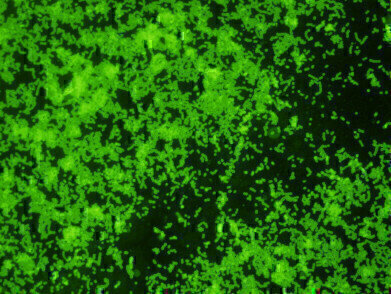

New Rabbit Monoclonal Antibody specific to GBS. This antibody reacts with the GBS Lancefield carbohydrate antigen found on the surface of the bacterium. This antigen can be released from specimens by extraction and detected via immunoassay methods. This new antibody reacts with all GBS strains tested but does not react with other Strep groups. This antibody joins ViroStat’s existing Rabbit Monoclonal Antibody to group A Streptococcus (GAS) as tools for rapid detection.